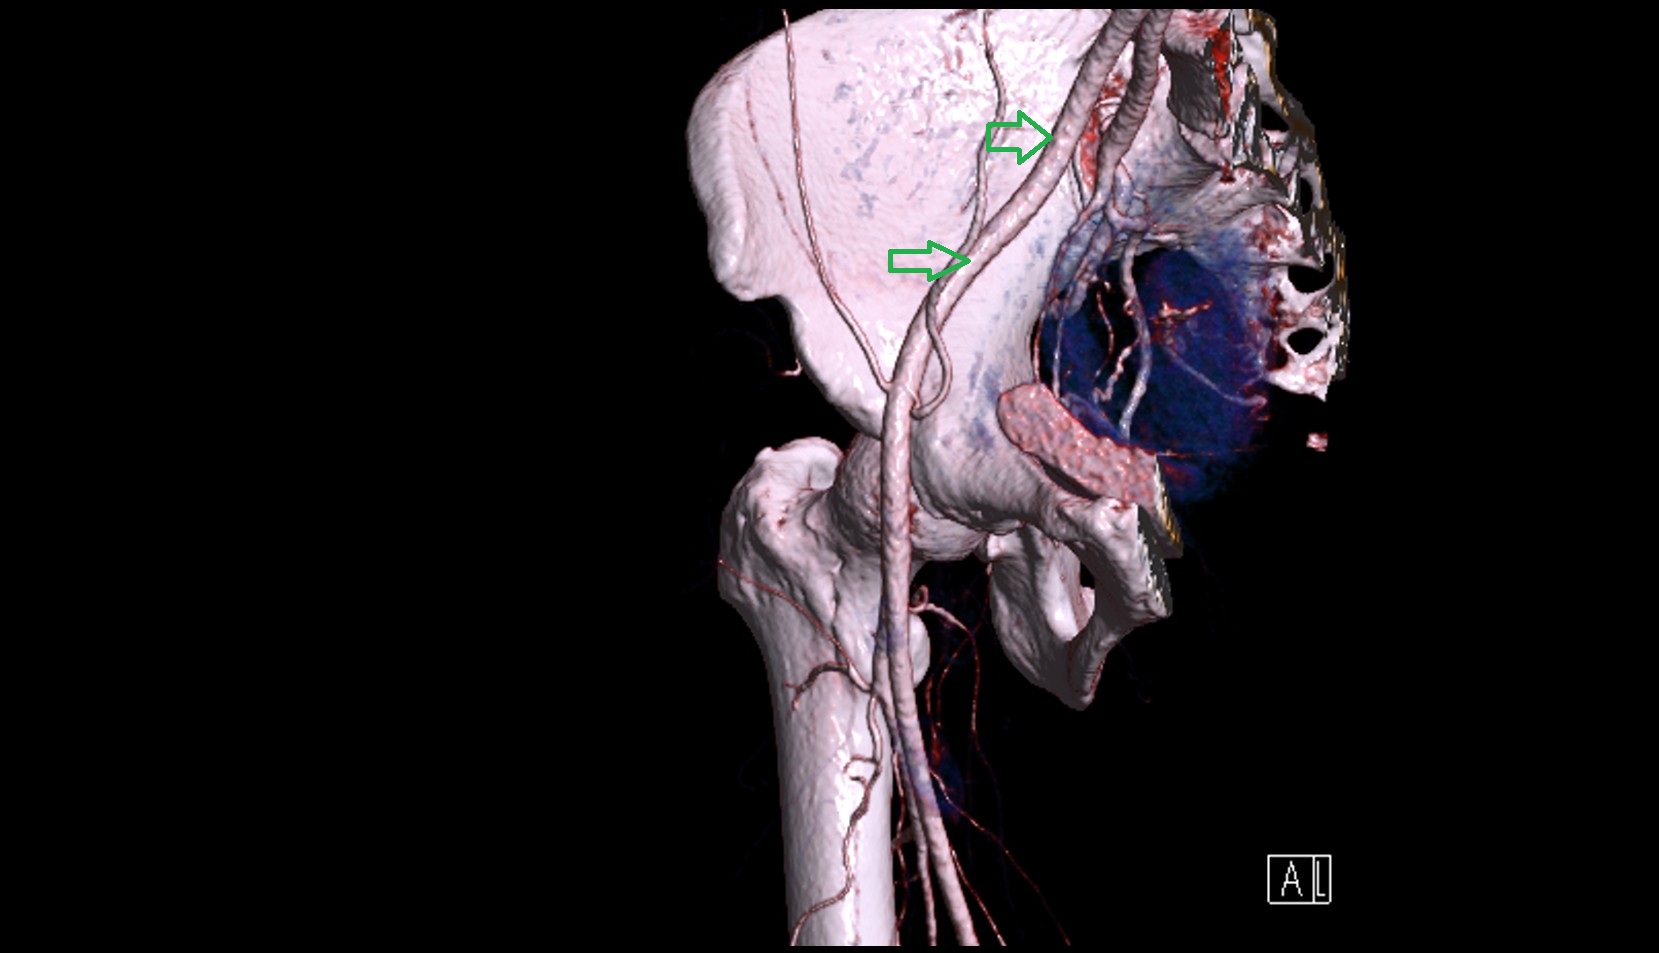

- External iliac artery

- Internal iliac artery

- common iliac artery

- Aortic bifurcation

- External iliac vein

- Internal iliac vein